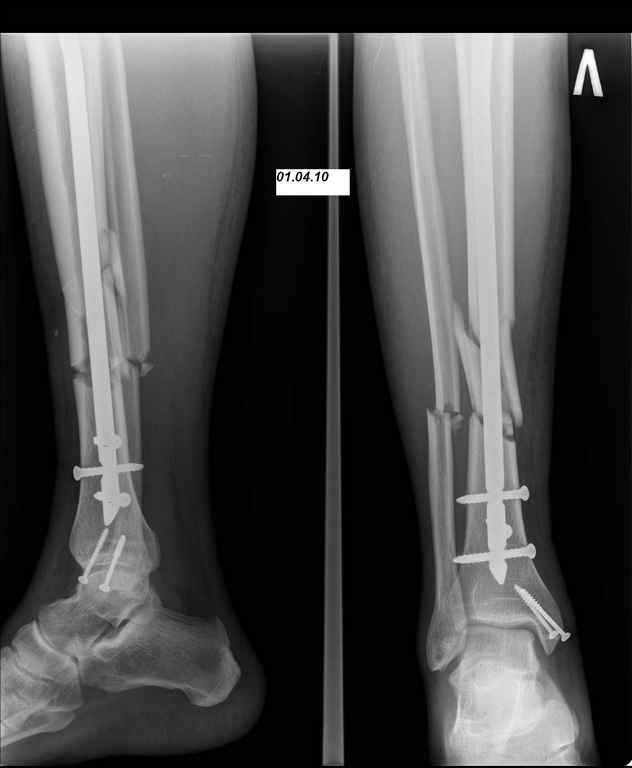

07.04.10 госпитализирован с диагнозом: Нагноение парафрактурной гематомы. При поступлении отек, болезненность при пальпации, гиперемия кожи по передней поверхности, пальпаторно флюктуация в месте перелома, местное повышение температуры кожи. выполнена пункция гематомы, получено 40 мл гнойно-геморагического пунктата. Взят бак посев (S. aureus, чувствительный ко всему что у нас есть). В место флюктуации введен раствор Новокаина 1%-30 мл+Гемтамицина 2,0 мл. Сформировался свищ в месте пункции, который закрылся через 10 дней. Проводились внутрикостные инъекции антибиотика (Кламосар, полусинтетический пенициллин, бета-лактамный) в левую пяточную кость №10. Температура за период госпитализации не выше 37,2С. По анализам небольшой лейкоцитоз. Свищ закрылся, локально гиперемия, отек, местное повышение температуры регрессировали. Выписан. И опять пропал. Травмполиклинику не посещал, на контрольные осмотры к лечащему врачу не приходил.

И вот опять объявился. Снимки и фотографии в приложении(первичные потеряны). Около 1 месяца назад появились боли в области нижней трети голени в проекции дистальных блокирующих винтов, передвигался с нагрузкой 50% (сам для себя так решил, сам себе разрешил). Путешествовал по Волгоградской области, обратился к травматологу, со слов перевязывали, лечили антибиотиками. Лучше не стало. Вернулся домой.

Вчера госпитализирован в отделение. Локально умеренный отек, кожная температуа не повышена. По передней поверхности в области дистального блокируюшего винта свищ, скудное гнойное отделяемое, винт удален на перевязке зажимом. «Старый» свищ не функционирует. Взят бак. посев, ждем результат.

Во первых штифт тонкий, во вторых коротккий. Не смотря на то что дистальное блокирование выполнено 3 винтами, связь с коротким дистальным отломком получиласть слабоватая если учесть активный образ жизни пациента и его "ненадежность" как выразился Александ Николаевич.